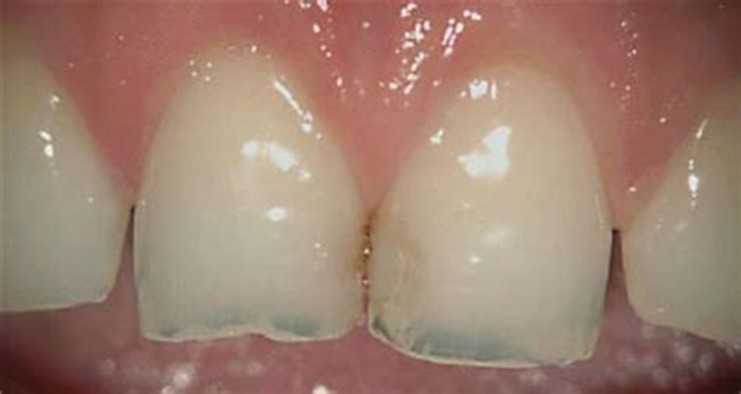

Demineralized Chipped and Transparent Teeth

Another implication of Vitamin K-2 deficiency would be the density of your teeth. If your teeth are thinning, looking more transparent, or have lots of dental cavities (even if you brush and floss daily), then your Vitamin K-2 may be low. At deficiency levels, your teeth will slowly demineralize, making them very susceptible to chipping and decay.